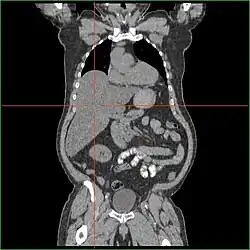

Hepatomegaly

Impairment in the liver's ability to perform gluconeogenesis leads to clinically apparent hepatomegaly. Without this process, the body is unable to liberate glycogen from the liver and convert it into blood glucose, leading to an accumulation of stored glycogen in the liver. Hepatomegaly from the accumulation of stored glycogen in the liver is considered a form of non-alcoholic fatty liver disease. GSD I patients present with a degree of hepatomegaly throughout life, but severity often relates to the consumption of excess dietary carbohydrate. Reductions in the mass of the liver are possible since most patients retain residual hepatic function that allows for the liberation of stored glycogen at a limited rate.

GSD I patients often present with hepatomegaly from the time of birth. In fetal development, maternal glucose transferred to the fetus prevents hypoglycemia, but the storage of glucose as glycogen in the liver leads to hepatomegaly. There is no evidence that this hepatomegaly presents any risk to proper fetal development.

Hepatomegaly in GSD type I generally occurs without sympathetic enlargement of the spleen. GSD Ib patients may present with splenomegaly, but this is connected to the use of filgrastim to treat neutropenia in this subtype, not comorbid hepatomegaly. Hepatomegaly will persist to some degree throughout life, often causing the abdomen to protrude, and in severe cases may be palpable at or below the navel. In GSD-related non-alcoholic fatty liver disease, hepatic function is usually spared, with liver enzymes and bilirubin remaining within the normal range. However, liver function may be affected by other hepatic complications in adulthood, including the development of hepatic adenomas.

Treatment standards dictate regular observation of the liver by MRI or CT scan to monitor for structural abnormalities. Hepatic adenomas may be misidentified as focal nodular hyperplasia in diagnostic imaging, though this condition is rare. However, hepatic adenomas in GSD I uniquely involve diffuse Mallory hyaline deposition, which is otherwise commonly observed in focal nodular hyperplasia. Unlike common hepatic adenomas related to oral contraception, hemorrhaging in GSD I patients is rare.